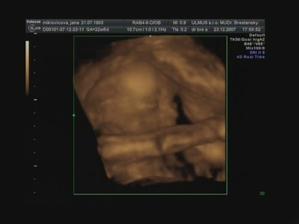

Emuška

Ahojte už som tu z 1,5cm som vyrástla na takúto krásnu slečnu moje meno je Emka a narodila som sa 4.4.2008 o 12:25 hod v Topolčianskej nemocnici vážila som 3510g a najviac na svete ma ľúbia maminka a ocinko